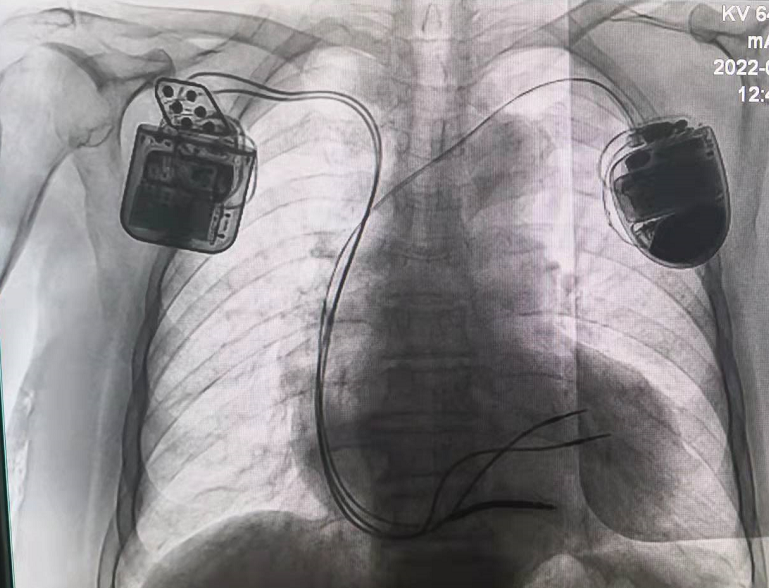

CCM联合ICD一站式手术需要在患者右心室内同时植入三根电极,且彼此间距不能小于2cm,才能确保ICD和CCM正常感知与起搏,避免相互信号干扰。同时考虑到除颤的效果,将ICD放置在左侧,CCM放置在右侧。

精准的放置三根导线对此次手术尤为关键,也是手术的难点,不仅要求导线参数满足要求,还需要兼顾三根导线放置的位置和间距,李耀东教授凭借着丰富的操作经验和精湛的导线操控技术,首先从左侧完成心尖部除颤电极的植入,随后从右侧先后植入两根主动起搏电极置于右室间隔。术中测试除颤电极阻抗600Ω,阈值0.6v,R波大于20mv;两根起搏电极的起搏阈值分别是1.6v(RV)和1.0v(LS),感知阈值均大于20mv,起搏阻抗均低于1200Ω,表明电极准确植入在健康心肌上。联合测试,三根电极均可以正常工作且彼此无干扰。国内首台CCM联合ICD一站式手术顺利完成,耗时90分钟。